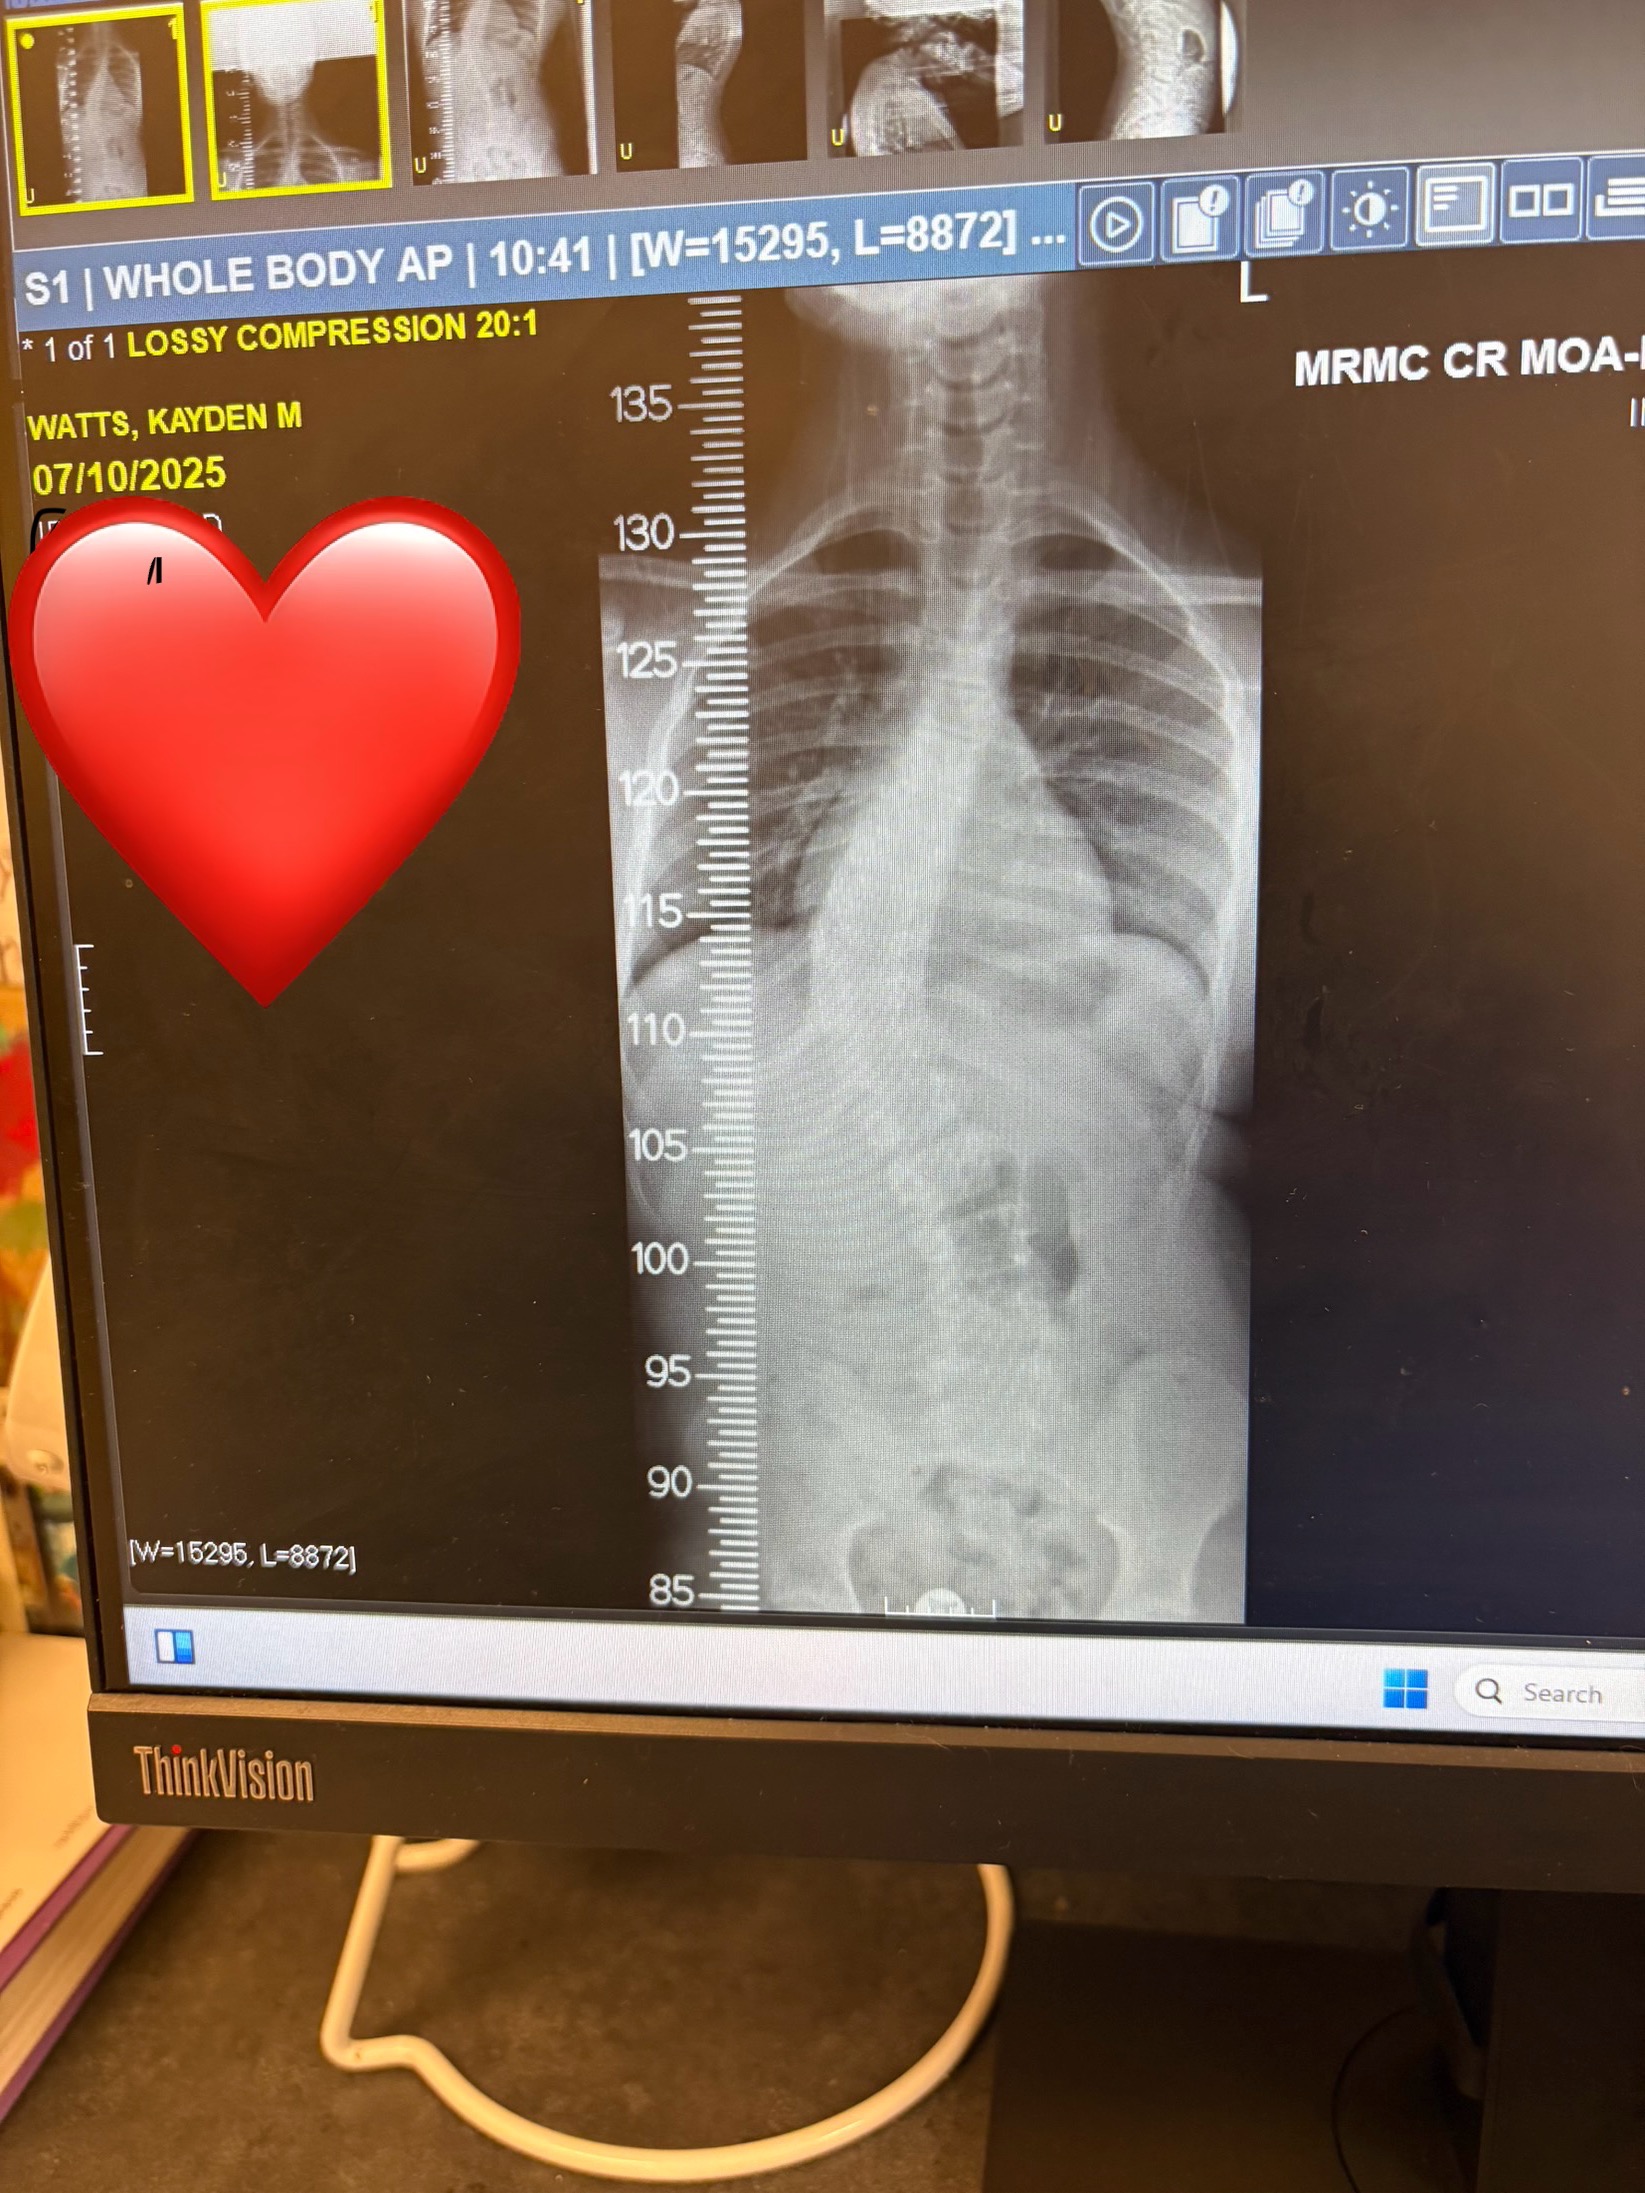

Hi, my name is Khadijah, and I’m reaching out as a mother asking for love, prayers, and financial support for my son as he prepares to undergo a major procedure to help correct his severe scoliosis.